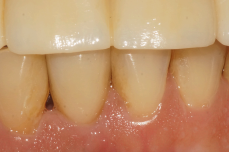

Na consulta seguinte, a coroa metalocerâmica foi instalada no elemento 41 e o orifício de acesso do parafuso foi restaurado com resina composta. Foi também realizada uma radiografia para posterior controle (Figuras 22, 23 e 24).

Após 12 meses, foi feita uma nova avaliação clínica e radiográfica, onde observou-se a boa manutenção dos tecidos peri-implantares (Figuras 25 e 26).